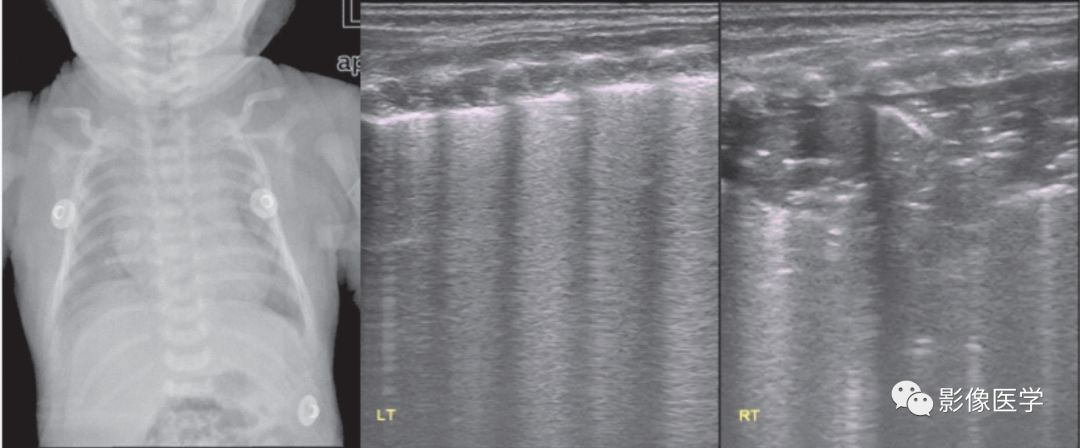

图6-16 宫内感染性肺炎:肺实变伴右侧胸腔积液

G1P1,胎龄38+3周,剖宫产分娩,出生体重3 270g。出生时无窒息。脐带扭转30余周,宫内窘迫,羊水Ⅲ°污染,无胎膜早破。出生后即见皮肤出血点。全身高度水肿,腹部皮肤出血点。产前超声提示胸腔积液+腹腔积液。胸部X线显示双肺模糊阴影,双侧肋膈角消失,右侧膈肌圆钝。肺脏超声提示双肺大面积实变、支气管充气征及双侧胸腔积液(右侧重)。